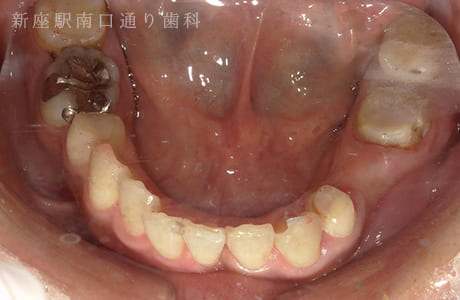

CASE.01

左下のフルジルコニアブリッジで

修復した症例

- 主訴

- 歯がないところを治したい

- 治療法

- 左下にフルジルコニアブリッジで修復

- 治療期間

- 1ヶ月半

- 費用

- ¥240,000(税込)

【リスク・副作用】

過度の咬合や衝撃で割れることがあります。治療直後は歯や歯茎に一時的な違和感や痛みが出ることがあります。